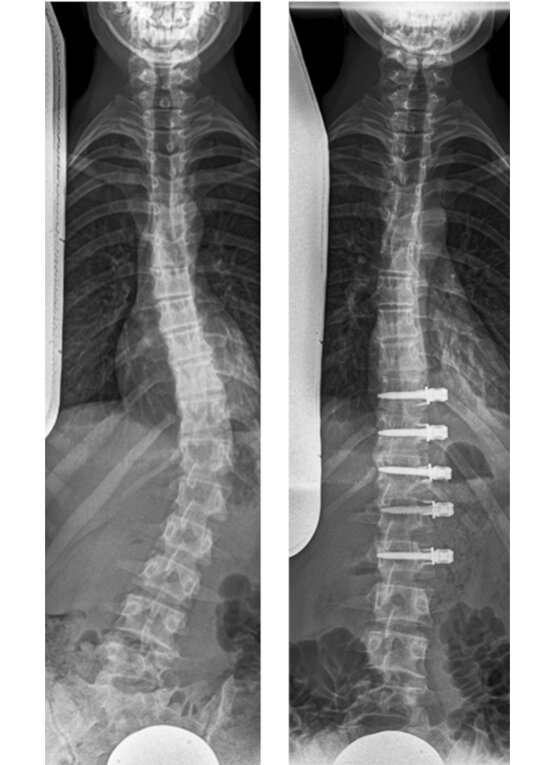

Magec-Stäbe

Die Magnetstäbe (Magec Stäbe, engl. Magec rods) werden nur oben und unten an der Wirbelsäule fixiert und dann in die Länge gezogen - ähnlich, wie das früher mit den Harrington Stäben erfolgte. 2 bis 4mal im Jahr wird über einen Magneten der Stab um einige Millimeter verlängert, bis die erforderliche Größe erreicht ist. Anschließend wird er wieder entfernt und eine konventionelle Spondylodese und Korrektur durchgeführt.

Magec rods: Beispielverlauf mit Wachstumsstäben

Der Wachstumsstab dient also vor allem dazu, die Zeit bis zur endgültigen Skoliose-Operation zu überbrücken, wenn eine Korsettversorgung nicht ausreichend ist. Auch wenn der Knochen noch nicht fusioniert (versteift) wird, ist man damit nicht beweglicher. In dem Bereich, in dem der Stab angebracht ist, ist die Wirbelsäule komplett unbeweglich. Die OP-Strecke ist in der Regel länger als bei den modernen Fusionsverfahren und da immer die Gefahr der Stablockerung oder des Stab-Bruchs besteht, ist man sportlich sehr eingeschränkt. Manchmal kommt es sogar zu einer spontanen Fusion der Wirbelsegmente allein durch die Ruhigstellung. Daher wird diese OP-Methode nur empfohlen, wenn eine Korsettbehandlung nicht möglich und die Patientinnen und Patienten für die endgültige OP noch deutlich zu jung sind. Für viele sehr junge Patientinnen und Patienten sind die Magnetstäbe die einzige Möglichkeit.